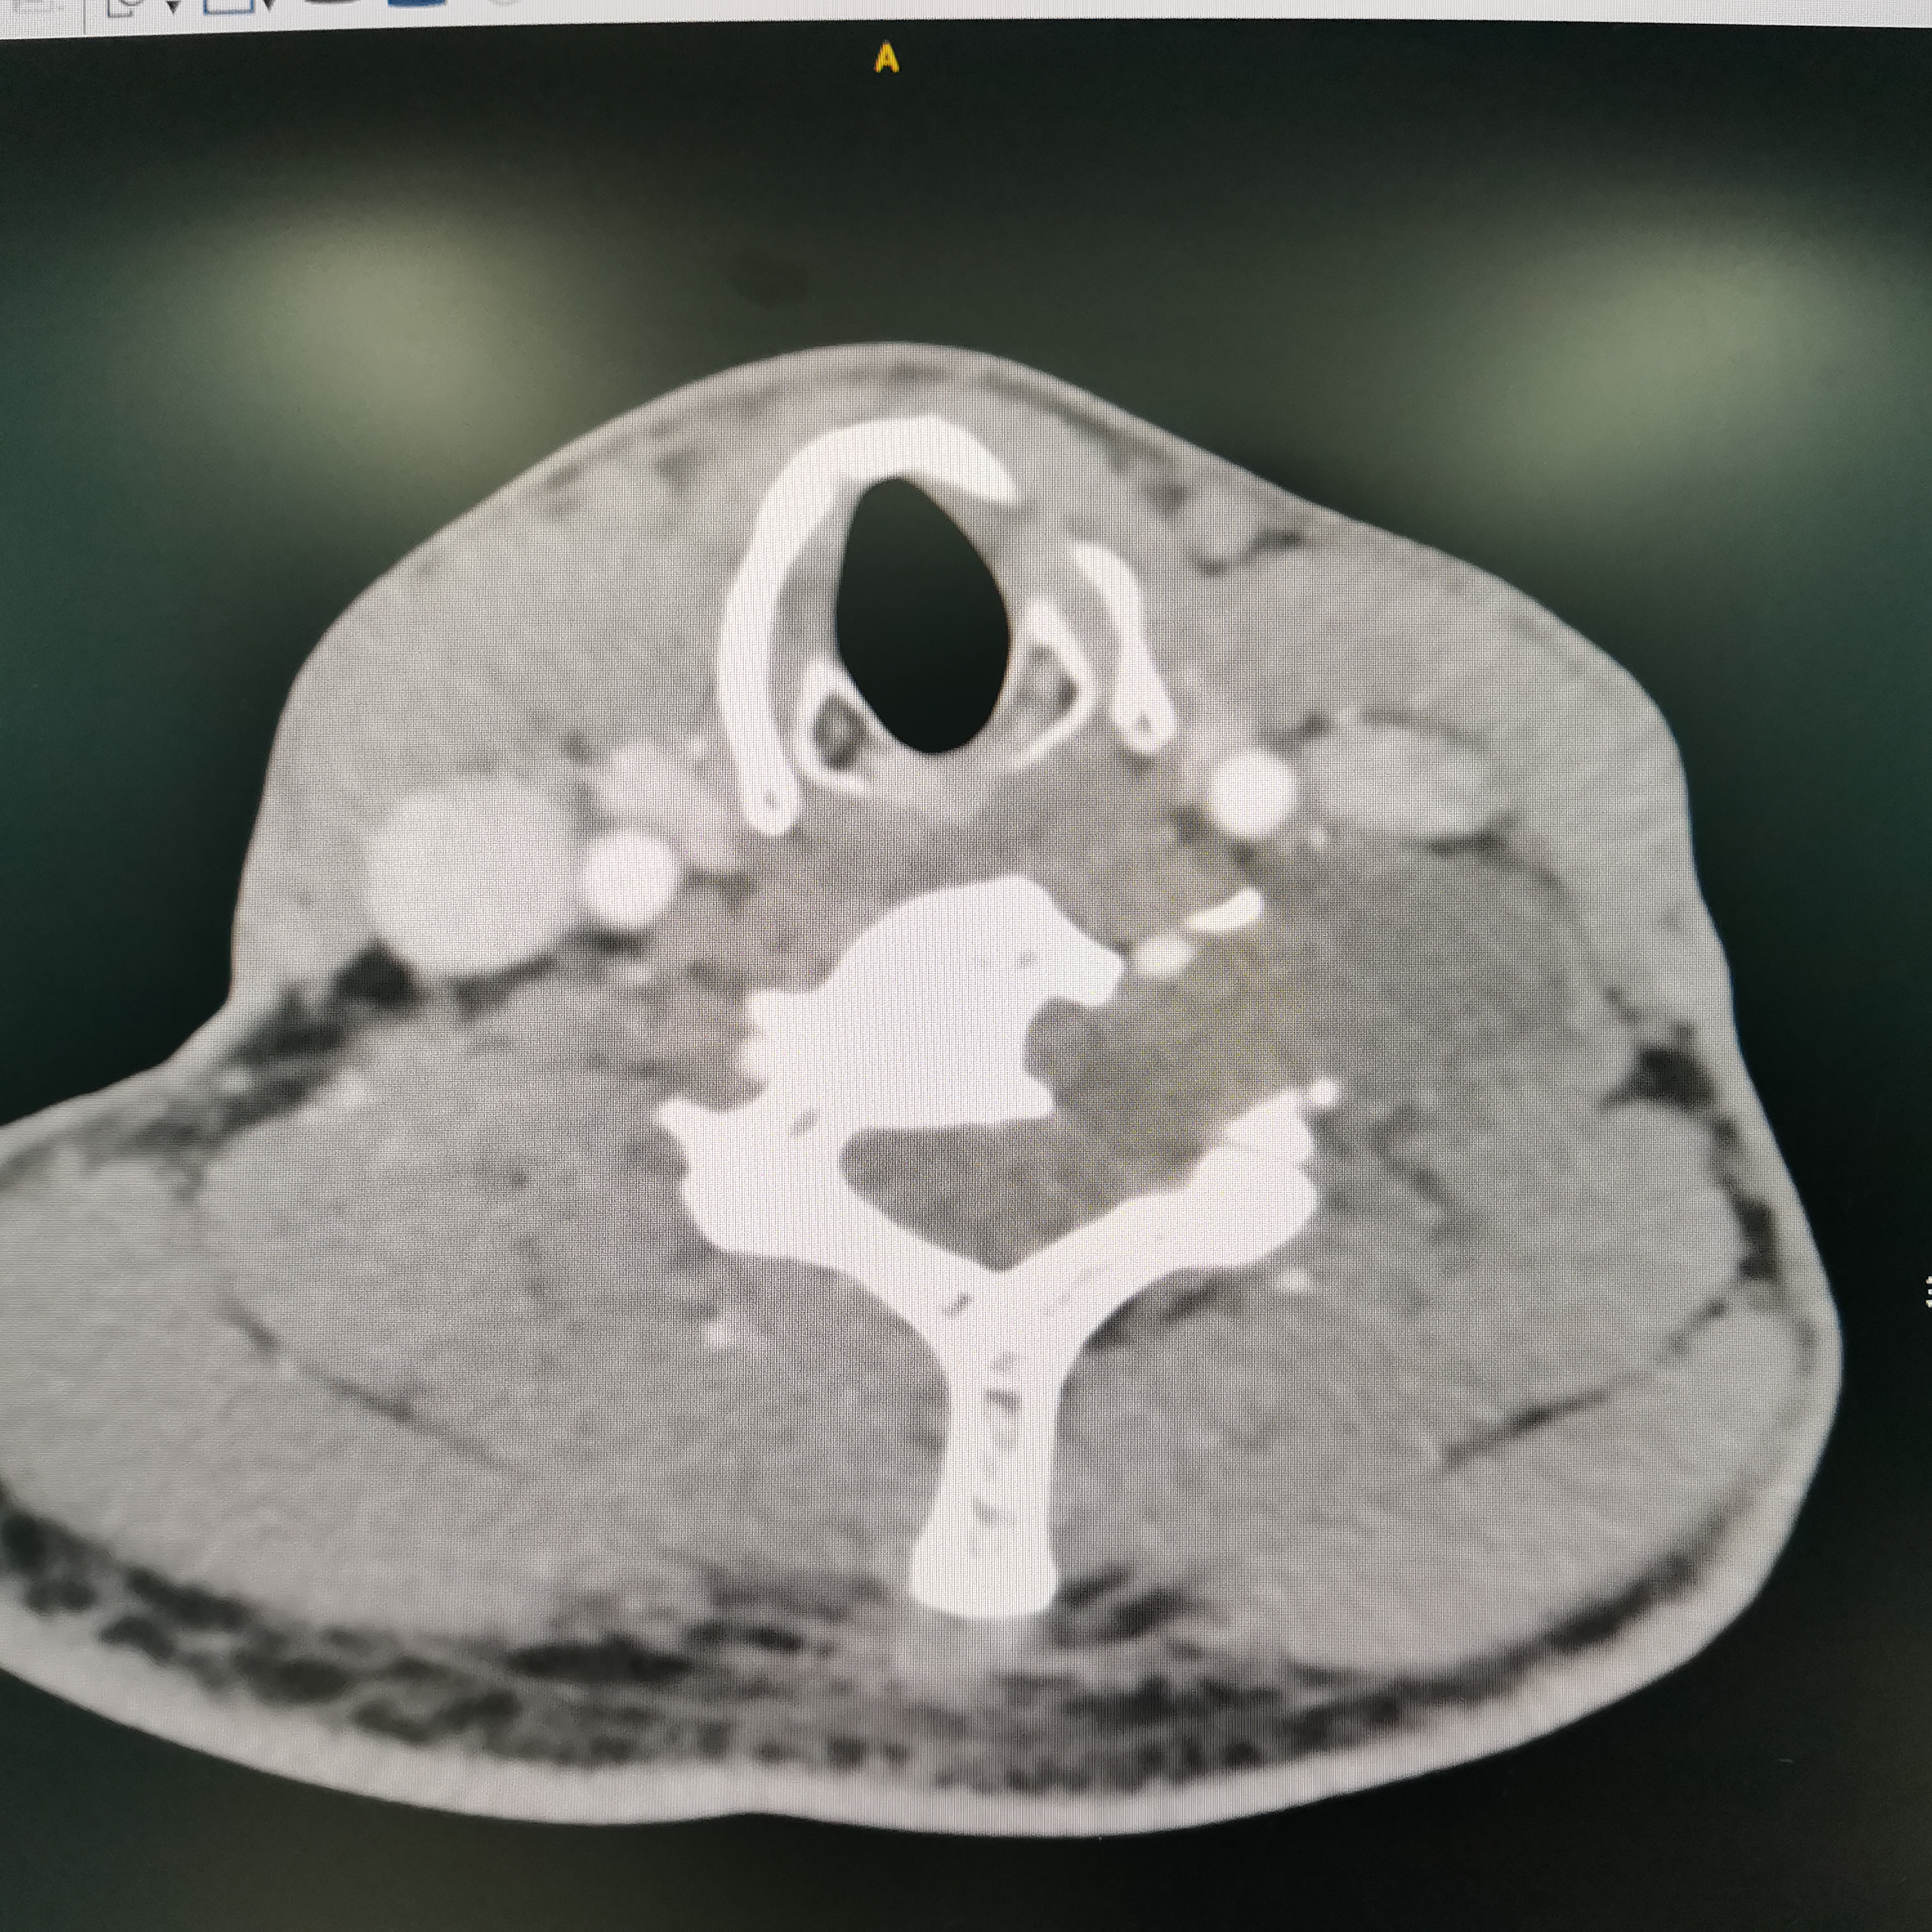

颈椎哑铃型神经纤维瘤,椎间孔汇合,安全又便于操作~